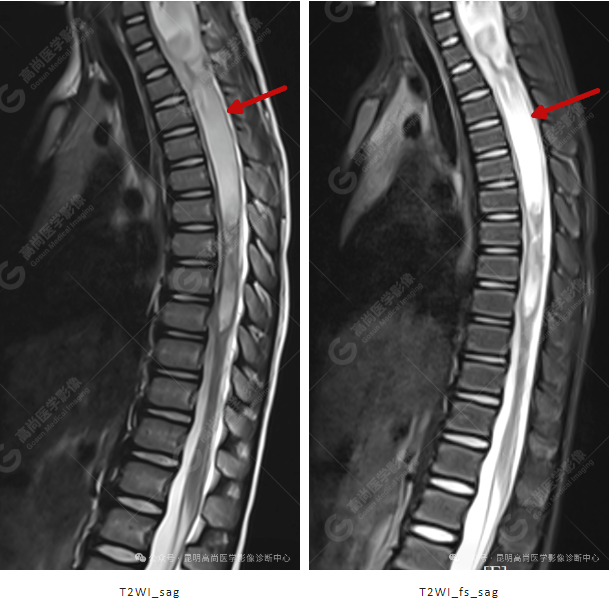

颈 3-5 层面颈后部软组织不规则片状异常信号影,脊膜膨出可能;颈 3、4 棘突局部显示不清;颈胸髓内(约颈 3-胸 9 椎体水平)异常信号影,考虑囊肿并局部颈髓空洞可能,肿瘤或其他待排;请结合临床及相关检查。